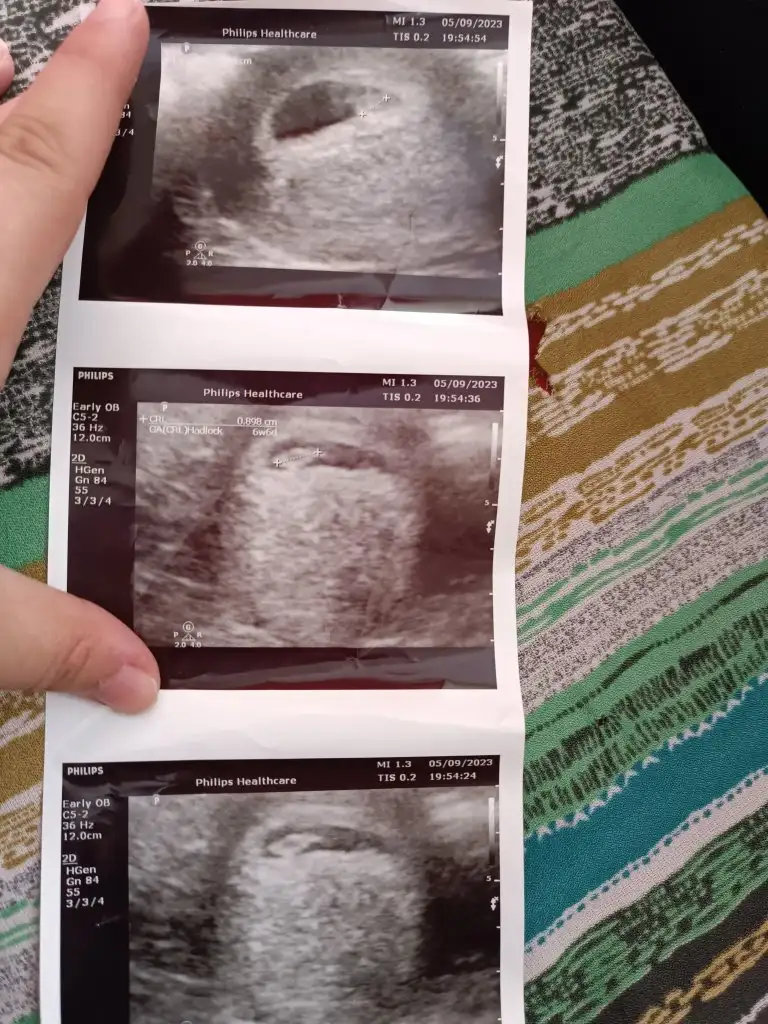

Merhaba ramzi teorisini baz alarak bakmıyorum kesenin konumuna ve iç gudulerime göre tahminde bulunuyorum :) önemli olan tabi sağlıklı olması Allah kucağınıza almayı nasip etsin inşallahEki Görüntüle 3296800 bana da bakar mısın rica etsem ,doktor 3 resim vermiş ilki başka açıdan diğerleri başka açıdan anlayamadım açıkçası.bebeği sağda hissediyorum.ramzi teorisi kesin tutuyor mu

çok teşekkür ederim Amin inşallahMerhaba ramzi teorisini baz alarak bakmıyorum kesenin konumuna ve iç gudulerime göre tahminde bulunuyorum :) önemli olan tabi sağlıklı olması Allah kucağınıza almayı nasip etsin inşallahbence erkek

Ramzi teorisi okudum yüzde 97 dogruymuş.Ama neye göre bakcam ultrasona bilemedim. Size sormak istedim Bebeğim sağa daha yakın sanki bası da solda ayakları sağa bakıyor yani. Anlamadım ben. Sağlıklı olsun tabi kız erkek fark etmez ama merak ettim. İlk foto 5+5 iken 2.foto 9+3ken